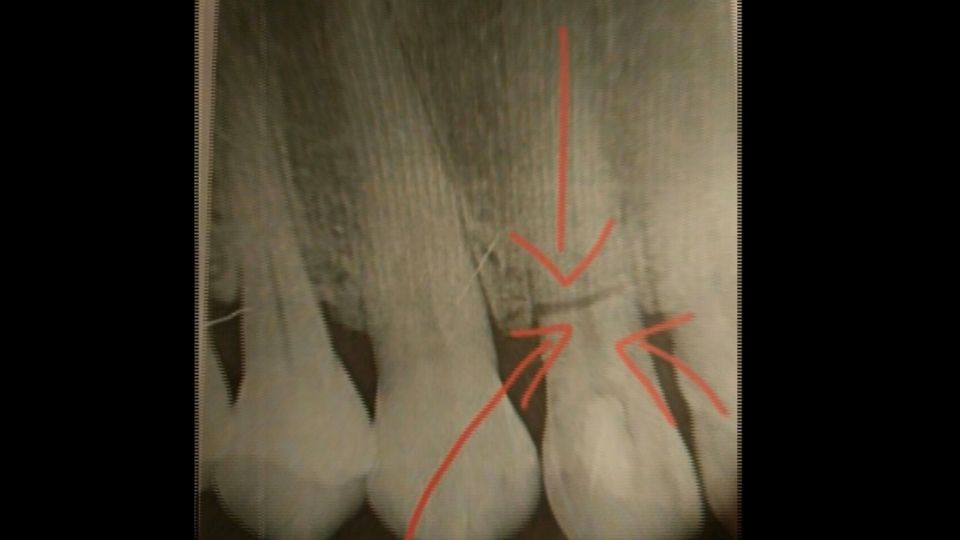

吃「淡水阿給」竟斷牙?名店遭告「過失傷害」

新北市淡水老街,知名的阿給老店遭告「

過失傷害

」原因竟然是因為,有顧客吃了阿給後,牙齒斷裂!但「阿給」是軟軟的豆皮裡面,包裹滑嫩的冬粉,怎麼會害顧客

斷牙

呢?我們深入追蹤,疑似是阿給的冬粉裡有小石頭,顧客一口咬下,牙齒在牙齦裡裂了一條縫,我們找到這名顧客「施先生」,他說已經跟店家簽了保密協定,不願多作說明,不過他透露,牙齒斷裂時真的痛到受不了,最後只得整顆拔掉!但阿給店家很無奈,表示開店將近半世紀了,第一次遇到。